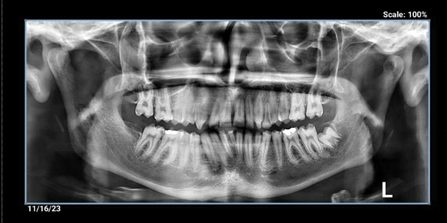

Clinical examinations showed primary canine on the left side of the maxilla and primary lateral teeth in the mandible. Periapical and panoramic radiography (Figure-2) and cone-beam computed tomography (CBCT) were taken. The graphic view consisted of a unilocular radiolucency with a well-defined boundary in the anterior maxilla, with some calcification. External root resorption was also observed in the related tooth, with buccal cortical plate extension (Figures-3a,3b).

Figure 2. OPG showing a round oval radiolucency around UR2 root